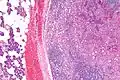

Histopathologic features

Basophilic, bland cells similar to acinar cells. Growth pattern: solid - acinar cells, microcytic - small cystic spaces mucinous or eosinophilic, papillary-cystic - large cystic lined by epithelium, follicular - similar to thyroid tissue.

These tumors, which resemble serous acinar cells, vary in their behavior from locally aggressive to blatantly malignant.